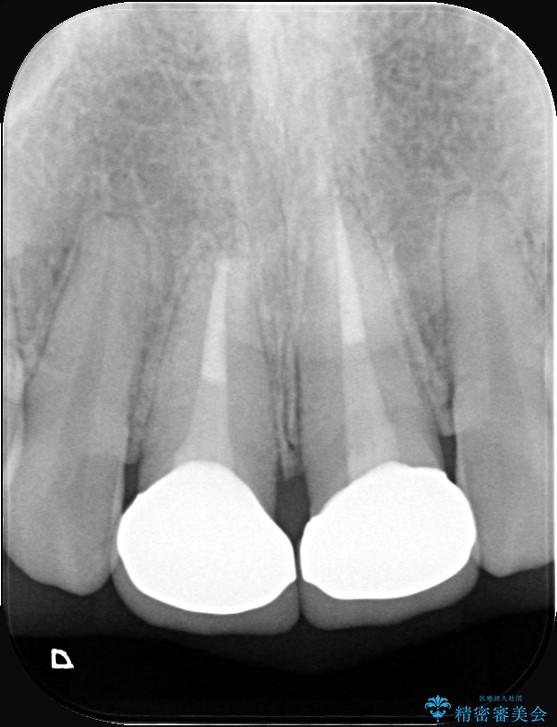

精密検査の結果、単に被せ物が合っていないだけでなく、その下の歯の根の治療(根管充填)が不十分で、再感染のリスクが高いことが分かりました。そのため、被せ物を新しくする前に、まず顕微鏡などを用いた精密根管治療を行いました。その上で、最も見た目が自然なオールセラミッククラウンで修復する計画です。これにより見た目の改善と歯の寿命の長期化を目指しました。

治療は、再感染の原因となっていた粗な根管充填材を丁寧に取り除く精密根管治療から開始しました。治療中はラバーダムと歯科用顕微鏡を使用し、根管内を徹底的に清掃・消毒。根の先まで緊密に薬を詰めることで、再発リスクを最小限に抑えました。根管治療の完了後、歯ぐきの状態を整え、周囲の歯と調和するオールセラミッククラウンを作製。金属を一切使わないため、透明感のある自然な仕上がりとなり、長年の見た目のコンプレックスも解消。歯の内部から表面までを根本的に改善することができました。